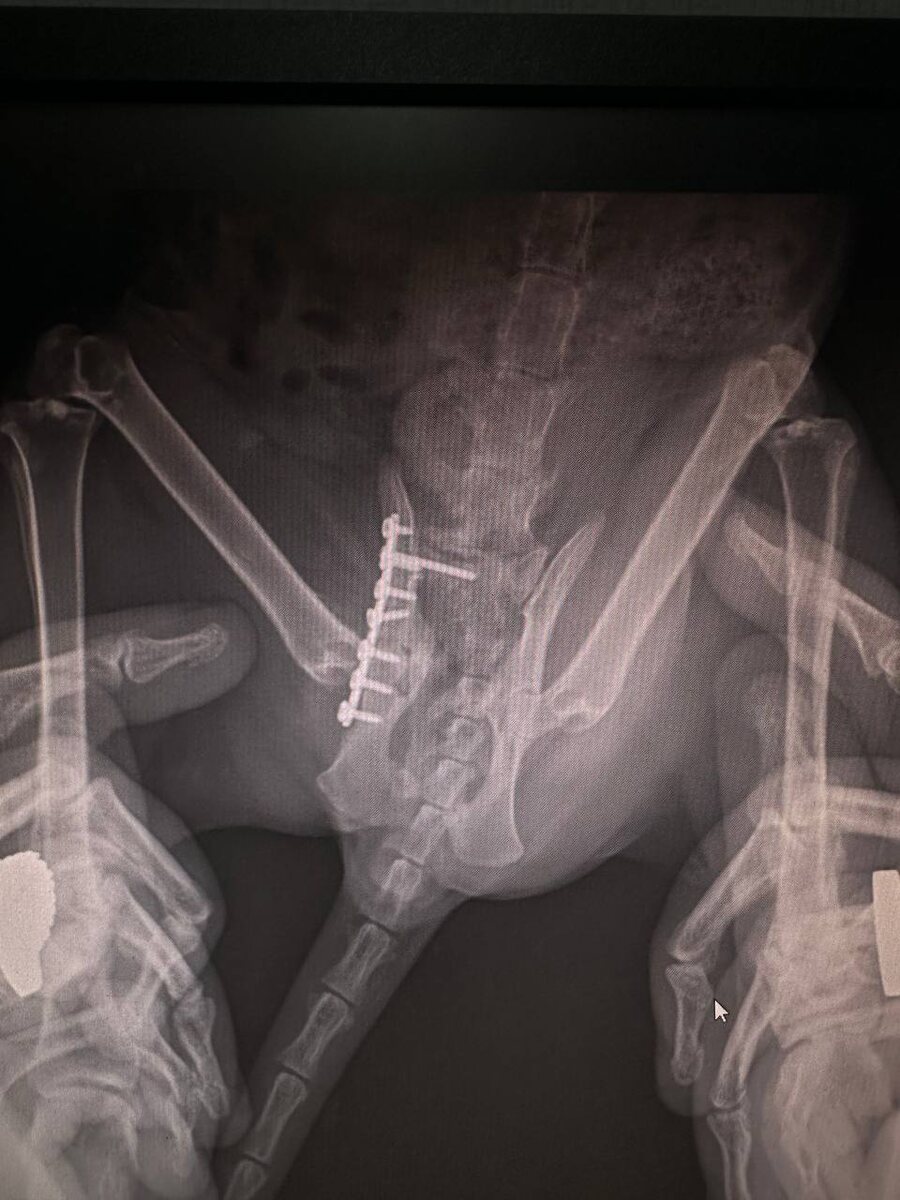

Герда 🥹🙏 всё на месте. Нам разрешили свободный выход из клетки 🥹🙏🙏🙏наконец-то С 26 декабря 2025 г бедненькая малышка передвигалась по пластунски в клетке с низким потолком, который наращивали специально, чтоб она не могла вставать/опираться на лапу. Герда пострадала в ДТП, получив 4 перелома, три из которых были очень серьезными. Следующая поездка в Кемерово через месяц и там уже принятие решения об изъятии металлоконструкции и об операции, связанной с одним из переломов. Сердечно благодарим Елену и Сергея за очередную поездку на межгород с🥹🙏❤️‍🔥❤️‍🔥❤️‍🔥 Сердечно благодарим всех, кто с нами 🙏❤️‍🔥❤️‍🔥❤️‍🔥 Благодаря всем Вам, у маленьких безмолвных пушистых комочком - ЕСТЬ ШАНС НА ЖИЗНЬ 🙏🫶

Герда пострадала в ДТП, получив 4 перелома, три из которых были очень серьезными.

Следующая поездка в Кемерово через месяц и там уже принятие решения об изъятии металлоконструкции и об операции, связанной с одним из переломов.